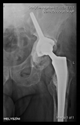

The radiological examination allowed us to verify the close bone-to-implant contact and the unchanged position of the implant during follow-up.

In all the cases operated with the above-described targeting procedure, the stems of the cups remained between the cortical bone surfaces without perforation of the linea terminalis, as shown by postoperative radiographs. There were no complicated surgical situations. In 16 cases, the wound healings were uneventful, and the hips were able to bear weight again after postoperative rehabilitation.